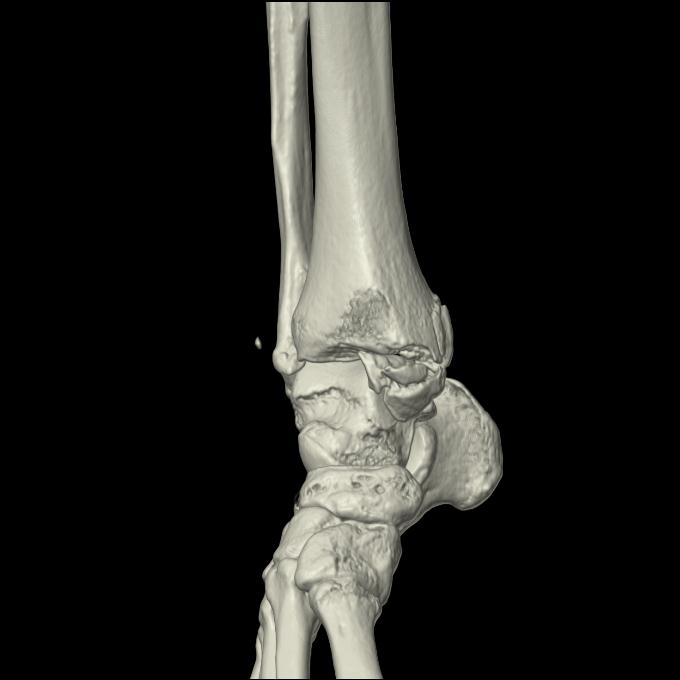

102755 1/4 2R 1/15 2R 右足関節 68歳女性 右三果脱臼骨折